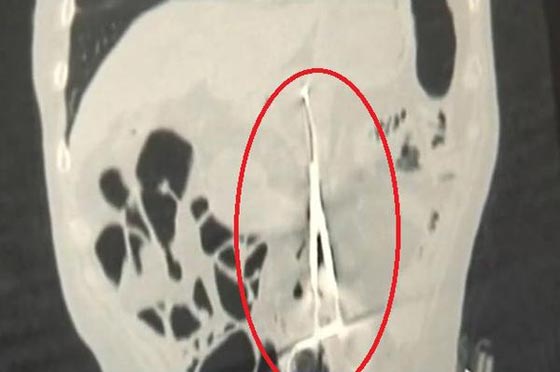

وحسب صحيفة "الديلي ميرور" البريطانية، فقد ظلّ الكازخستاني "كارب بونوماريوف" "53 عاماً" يعاني ألماً في معدته كلما تناول وجبة طعام أكبر من المعتاد، لكنه في الفترة الأخيرة عانى آلاماً شديدة بمعدته، وفقد شهيته، وهو ما دفعه إلى زيارة الطبيب. وجاءت المفاجأة حينما خضع "بونوماريوف" للكشف بأشعة "إكس"، وذهل الطبيب حينما وجد مقص الجراحة، والذي يبلغ طوله 20 سنتيمترا

ونقلت الصحيفة عن الطبيب "بورزهان إيباييف" "44 عاماً" قوله: "لم أر شيئاً كهذا في حياتي، يمكن أن ينسى الطاقم الطبي قطعة من القطن أو قماشة التنظيف، لكن أن ينسى مقصاً طوله 20 سنتيمتراً، فهو أمر غريب".وحسب الصحيفة: رفض "بونوماريوف" مقاضاة المستشفى، مشيراً إلى أنها أنقذت حياته حين أجريت له الجراحة منذ 12 عاماً، كما أن الطبيب الذي أجرى الجراحة توفّي منذ نحو عامين